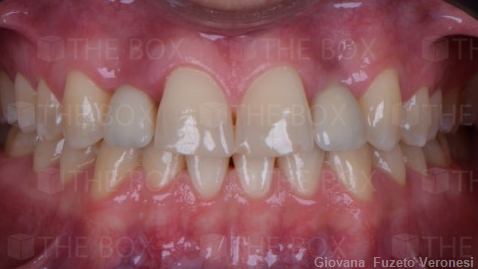

Infra bony defect one wall defect follow up 18 months show regeneration of buccal bone and interdental defect utilizing allograft bone substitute